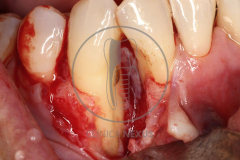

Tratamiento de defectos periodontales infraóseos en sector antero-inferior empleando gel de amelogeninas (Emdogain®) en combinación con un aloinjerto óseo (Biobank®). Paciente de 64 años, sin problemas médicos de relevancia, que presenta una periodontitis leve generalizada, pero asociada a presencia de defectos óseos verticales profundos a nivel de los espacios interdentales entre los caninos y los incisivos laterales inferiores. Tras la pertinente fase higiénica, se llevó a cabo una cirugía periodontal regenerativa, en la que, tras eliminar el cálculo subgingival (factor causal), se empleó una combinación de amelogeninas con un aloinjerto, para promover la regeneración tisular del periodonto perdido. Las imágenes clínicas y radiológicas, al año de seguimiento, reflejan un resultado terapéutico óptimo, con regeneración completa del tejido periodontal y mejora del pronóstico de los dientes involucrados.